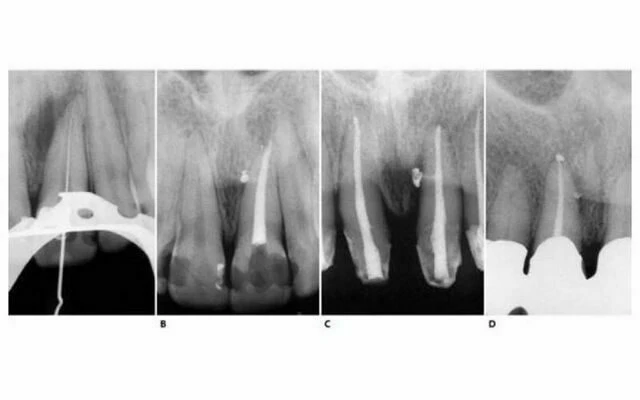

X-quang theo chiều gần xa

Hình 11.25. A. X-quang theo chiều gần xa  hình ảnh  răng cửa giữa trên. B. Sơ đồ biểu thị hình ảnh răng trước đó. C. Mũi khoan kim cương tròn sau khi hoàn thành pha xuyên qua. D. Sơ đồ của răng lúc này.